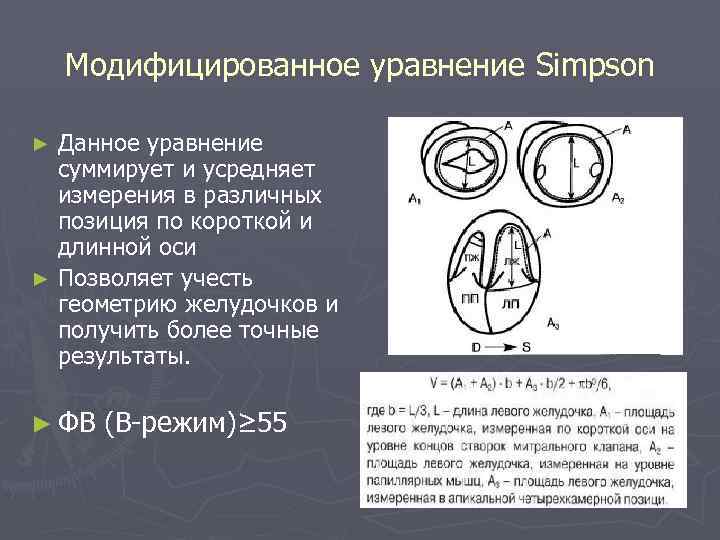

Модифицированное уравнение Simpson Данное уравнение суммирует и усредняет измерения в различных позиция по короткой и длинной оси ► Позволяет учесть геометрию желудочков и получить более точные результаты. ► ► ФВ (В-режим)≥ 55